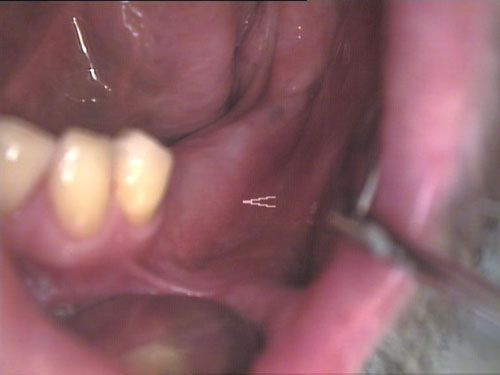

Zahnprothese mit Klammer